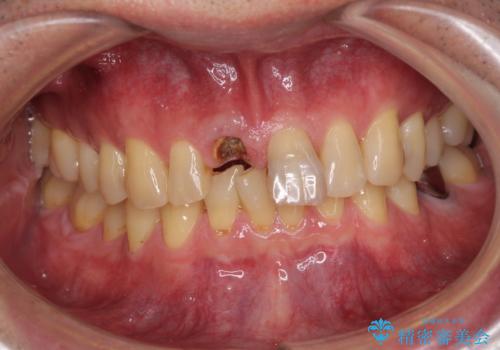

- 前歯の被せものが脱離したとのことで来院された患者様です。

診察の結果、前歯が縦に破折しており、抜歯が必要と診断されました。

補綴治療としては、インプラントあるいはブリッジの2つがありますが、患者様と相談した結果、インプラントによる補綴治療を選択することとなりました。